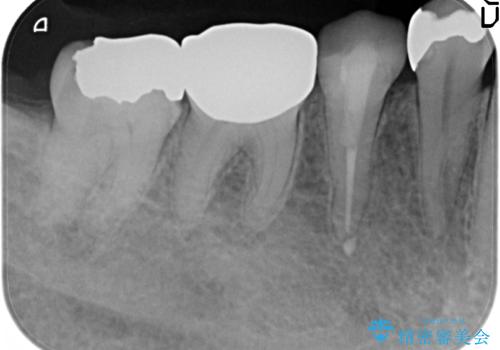

- 甘いものを食べると右下4番目の歯がしみるので診て欲しいといらっしゃった方の症例です。

古い銀歯と虫歯を除去後、PGA(ゴールド)インレーによる修復を行いました。